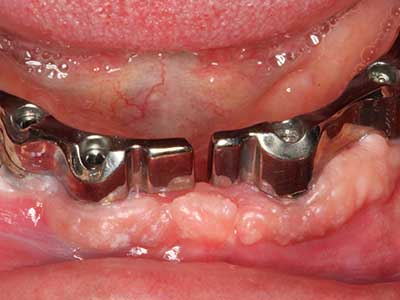

When surgical procedures are performed on bone in the immediate vicinity of sensitive structures such as blood vessels or nerves, rotary instruments pose a significant risk of iatrogenic injury. Piezoelectric devices can be helpful for preparation of bone covers and removal of hard tissue close to nerves, particularly for exposure of nerves after iatrogenic injury but also during nerve lateralization for resective and reconstructive procedures or implant placement (Fig. 17-20). Light contact between the piezotip and the nerve does not generally result in damage but proceeding incautiously with saw-like motions or attachments where a residual bone substrate remains may cause temporary or even permanent nerve damage. However, the risk of damage is considered to be substantially lower than when using saws or milling instruments (Pereira, Gealh et al. 2014).

Indication: Periodontal therapy

Marginal periodontal diseases are the main reason for extractions in advanced age. These diseases are primarily caused by bacterial colonization of the gingival pocket, which causes inflammation followed by loss of the periodontium. The formation of subgingival biofilms and concrements is a significant aetiological factor for marginal bone atrophy, so their removal is an important part of the treatment (Drisko 2014, Plessas 2014).

Initial and surgical treatment phases are differentiated in the treatment of marginal periodontitis. In addition to instruction in oral hygiene and motivating patients, both phases should include adequate cleaning of the root surface. In the regenerative setting an open access is generally preferred. The root surface can be cleaned by piezo surgery using special attachments, where instruments with different curvatures are used to reach areas that are difficult to access, such as furcations. The integrated irrigation in the system flushes the detached concrements and bacteria out of the pocket. Specialized systems such as the Piezomed also include application feedback to minimize the ablation of hard dental substance. The greater the pressure on the periodontal attachment the greater the reduction in the amount of ablation.